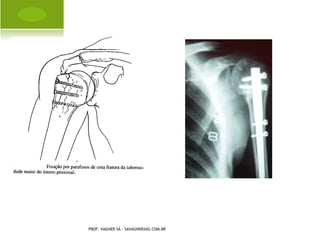

F RATURA - LUXAÇÃO OMBRO

T RATAMENTO CIRÚRGICO PROF.VAGNER SÁ - SAVAGNER@IG.COM.BR